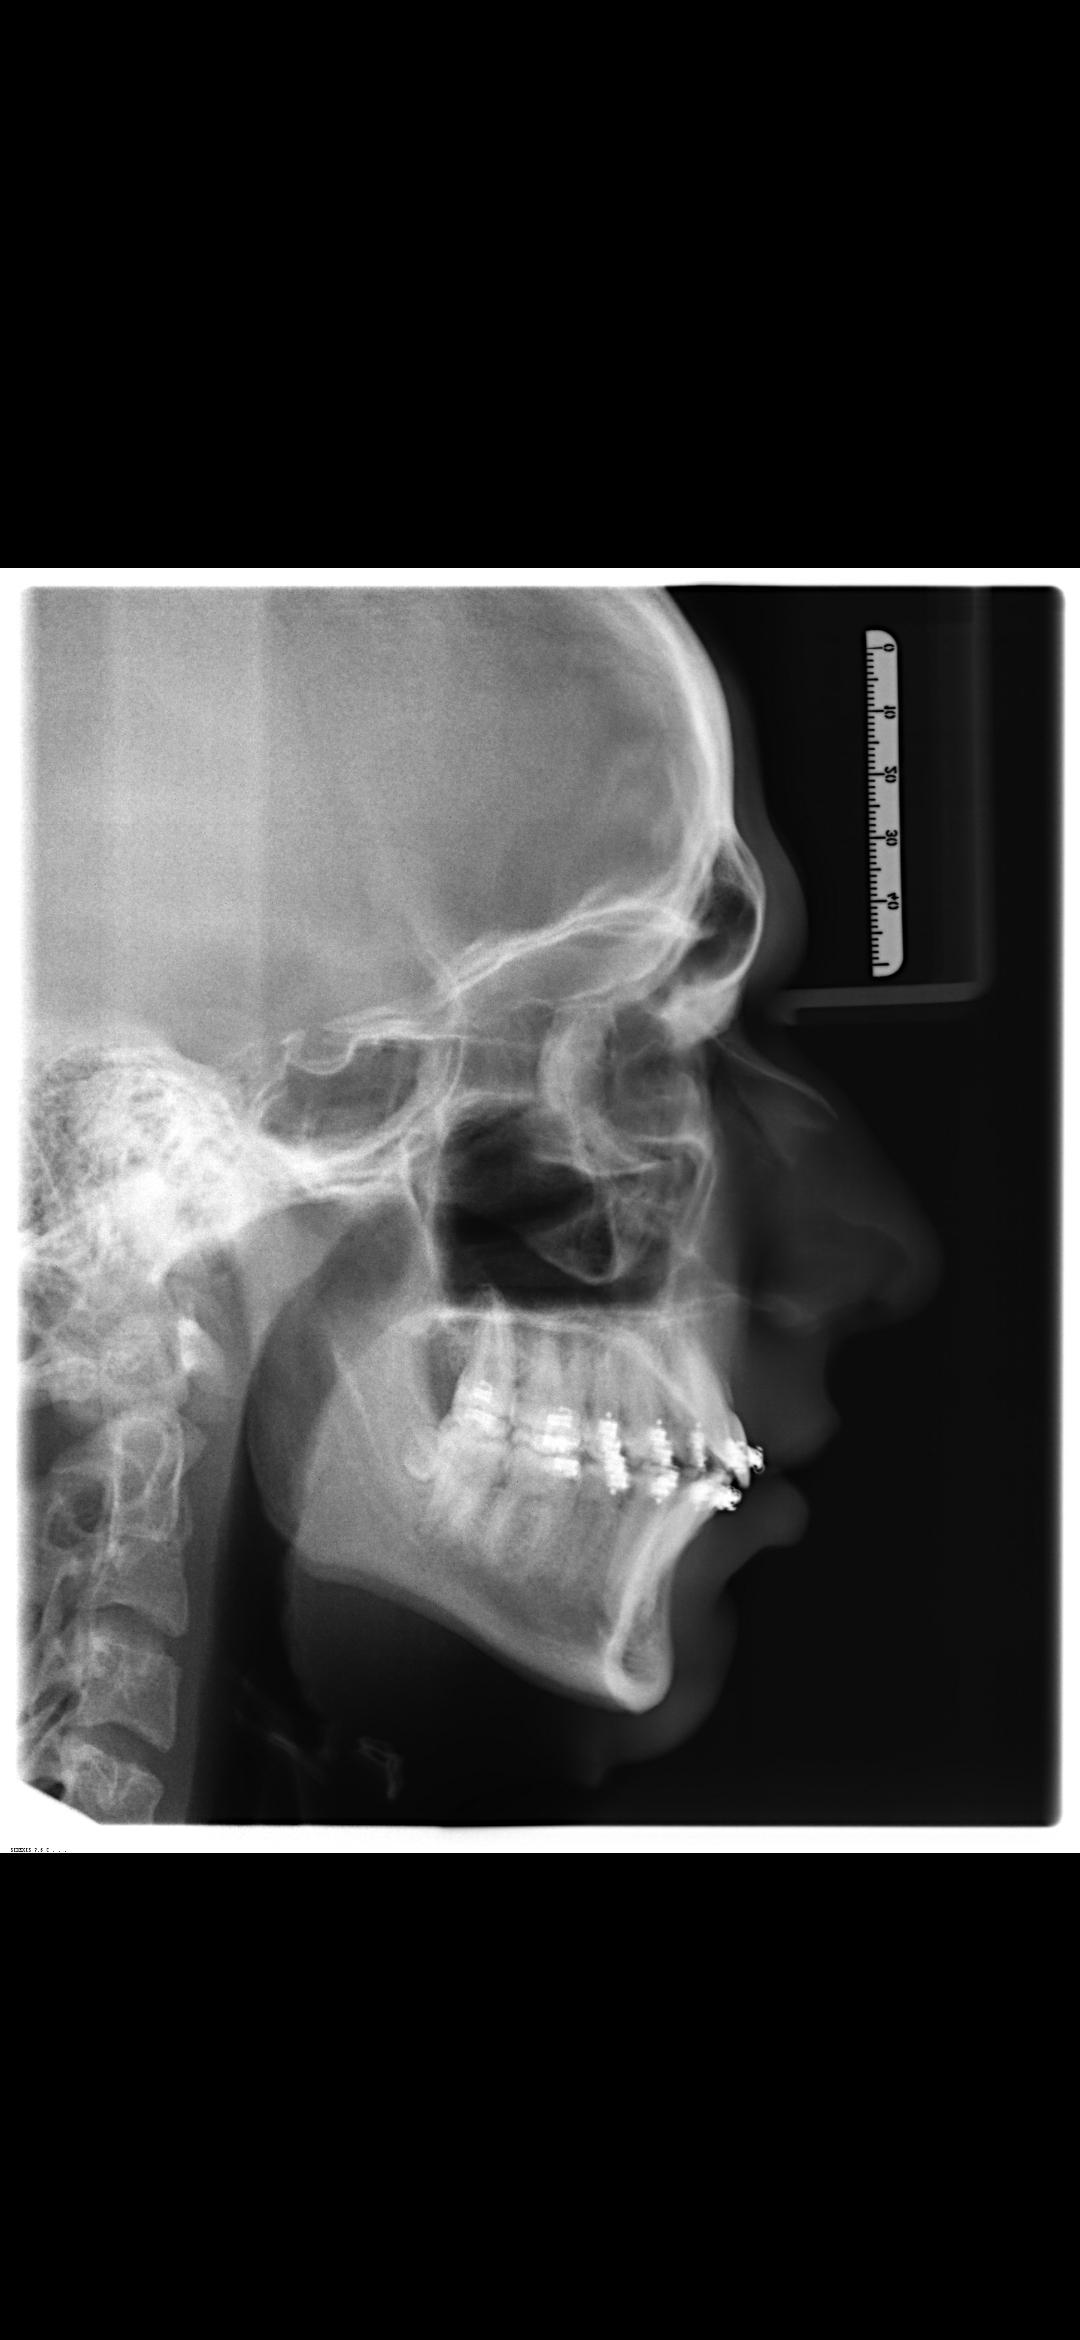

I'm planning my bimax surgery (which i'm getting in about 4 weeks) next week on wednesday. I've already made some plans, can yall tell me what you think of them considering my ceph?

It's in german, but the most important points are understandable (such as rotation and advancement)

Look at how wide the airway is, no way insurance is covering it.